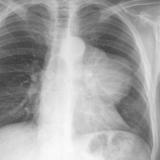

Case 9 Thymoma PA

Date: 04/04/2010

Views: 3176